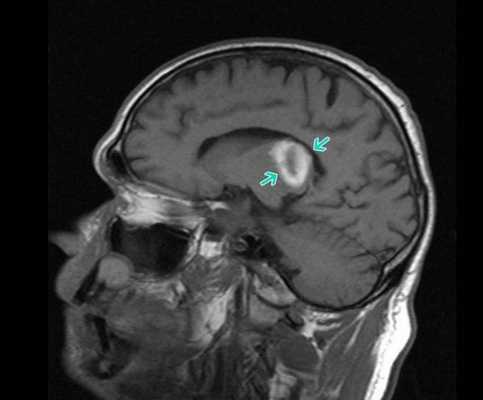

Очаг ишемии и некроза головного мозга (показан стрелками) на МРТ

Повреждения вертебрально-базилярного круга приводят к головокружениям, потере равновесия, возможна рвота. Ухудшается зрение, страдают мышцы глаза с пораженной стороны, снижается чувствительность половины тела.

Интракраниальное кровоизлияние на МРТ (стрелка указывает на гематому)

Кровоизлияния слабо определяются на магнитно-резонансных томограммах. При геморрагическом инсульте на МРТ гематомы представлены очерченными очагами с усилением сигнала (Т1-взвешенный режим).